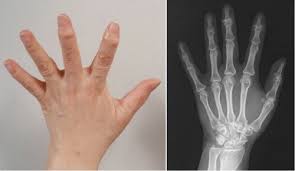

- 건선성 관절염: 건선 환자에게 발생할 수 있는 관절염으로, 피부와 관절 모두에 영향을 미칩니다.

손가락 관절 주변이 붓고 뜨거워질 수 있습니다. 이는 염증으로 인한 반응으로, 손가락을 움직일 때 더 심해질 수 있습니다. 부종이 지속되면 관절이 변형될 위험이 있습니다.

피부 변화

관절 주변의 피부가 붉어지거나 발열할 수 있습니다. 이는 염증이 있는 부위의 혈류가 증가하기 때문입니다.